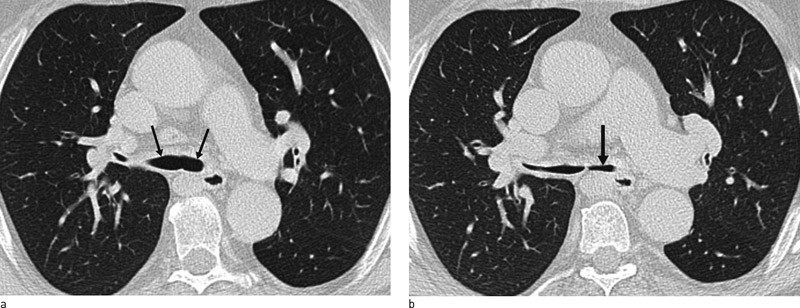

To måneder senere viste CT-undersøkelse av thorax patologiske funn. Det ble påvist veggfortykkelse oppimot 5 mm både i trachea og begge hovedbronkiene samt tydelig avsmalet lumen i hele forløpet til begge hovedbronkiene (fig 1). Denne gangen ble det også tatt bilder i ekspirasjon, som viste kollaps av hovedbronkiene til 4 mm (fig 2). Radiolog mistenkte trakeomalasi og anbefalte utredning med bronkoskopi. Påfølgende bronkoskopi viste tydelige tegn til kollapstendens i sentrale luftveier, mest uttalt i området rundt karina og venstre bronkialtre. Overflatisk bronkialbiopsi viste regelmessig slimhinne og noe arraktig fibrose, men uten bruskvev i prøvematerialet.

CT thorax er svært nyttig for vurdering av affeksjon av store luftveier. Typiske funn er veggfortykkelse og lumeninnsnevring i tra-chea, larynx eller bronkier og/eller ekspiratorisk kollapstendens i trachea og store bronkier (fig 1, fig 2). For å påvise kollapstendens i store luftveier er det helt avgjørende å ta tilleggsbilder i ekspirasjon, som hos denne pasienten, da vanlig CT i inspirasjon kan være helt normal. Selv om trakeomalasi er et karakterisk funn ved residiverende polykondritt, kan det ikke regnes for å være patognomonisk, da slike funn også kan forekomme ved Wegeners granulomatose og annen kronisk betennelse i luftveiene. Histologisk bekreftet diagnose med påvisning av kondritt i form av perikondrale lymfocyttinfiltrater er ønskelig (3). I praksis viser det seg dog ofte vanskelig å få dype nok biopsier med tilstrekkelig bruskmateriale.